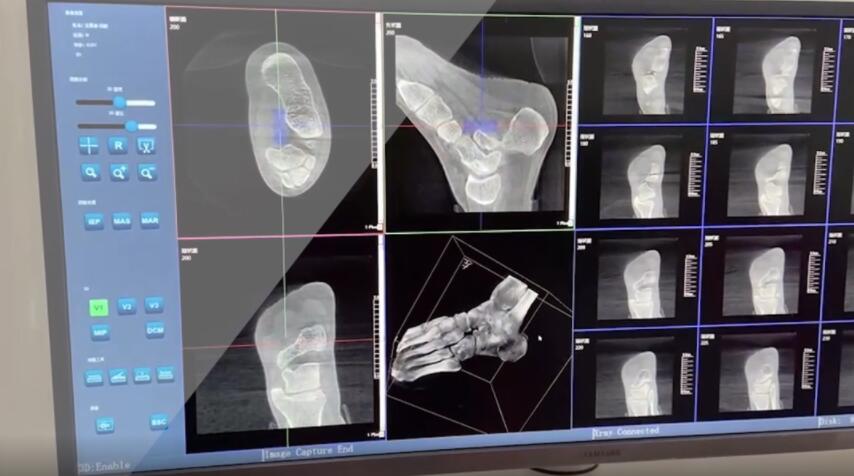

踝關節是人體中負重較大的關節,也是活動度較大的地方,所以對于足踝部位的關節內骨折,我們更需要做到“解剖復位”。對于這種關節內的骨折,尤其是踝關節內部的骨折,不僅需要進行X影像平片正側位的拍攝,由于在二維影像上無法判斷關節面的受損情況,往往還需要進行三維影像的檢查。

在術前,我們需要做三維掃描的CT檢查,我們必須要有CT的片子,還要有三維的重建。

在術中,我們怎么去判斷關節面平不平整呢?常規的正側位影像是不能判斷的。有些醫生為了準確的判斷,可能會選擇做開放性的手術,把關節暴露出來,在眼睛的直視下判斷關節面平不平整。但是關節全部打開,無疑增加了病人的創傷,而且增加了患者的恢復時間。所以如果在術中我們有三維影像的支持,對醫生做手術而言就會事半功倍,而且能夠大大的增加手術準確度,增加患者術后的預后。所以在術中有三維影像的支持是非常必要的!